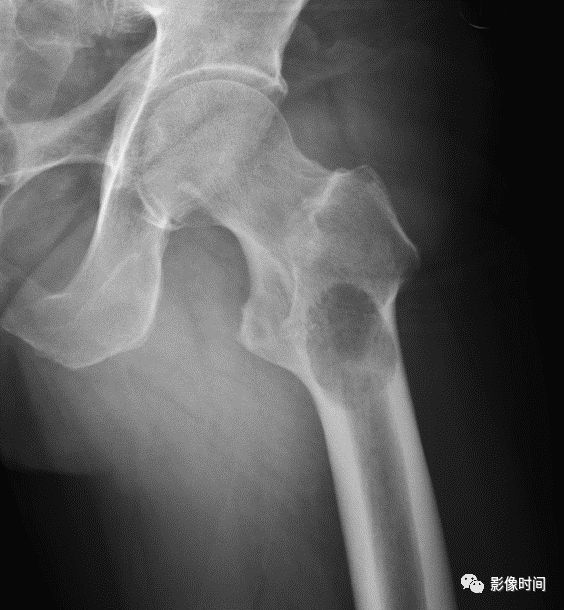

(一)地图样破坏 地图样破坏是指肿瘤组织在一个局部呈团块状生长造成界限清楚的骨质破坏(图 1、图 2、图 3、图 4)。

病灶可位于骨的中心或一侧部位,呈圆形、卵圆形密度减低区,与正常骨质分界清晰,边缘可有或无硬化带围绕,骨的形态无变化,病灶内可完全透亮或可见粗细不均、大小不等的残留骨嵴,内缘可光滑或呈分叶状压迹。

地图样破坏见于大多数良性肿瘤和肿瘤样病变如单纯性骨囊肿、骨纤维结构不良、血管瘤等、也可见于部分恶性骨肿瘤如骨转移瘤、骨髓瘤等。

图 1 地图样破坏:单纯性骨囊肿